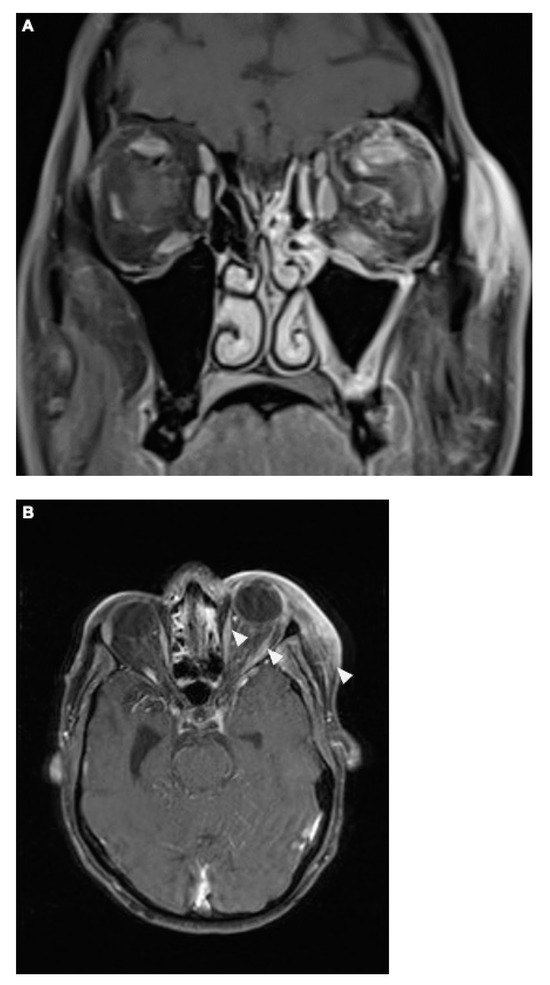

Figure 4.

The coronal T1-weighted post-Gadolinium magnetic resonance imaging (MRI) sequence revealed no definitive evidence of cavernous sinus thrombosis. However, venous dilation in the left superior ophthalmic vein was noted, along with significant phlegmonous enhancement at the apex of the left orbit, involving the left superior rectus muscle and potentially the optic nerve. Adjacent sinusitis was observed in the left frontal, ethmoid, sphenoid, and maxillary sinuses, accompanied by mild swelling of the left eyelid and inflammation of the adjacent subcutaneous tissue (A). The axial T1 post-Gadolinium MRI sequence (B) demonstrated contrast-enhanced protrusion of the left eye muscles, particularly affecting the superior rectus muscle. This indicated ongoing inflammation, though there was a slight reduction in the extent of optic nerve involvement compared to earlier scans, suggesting a partial therapeutic response. Importantly, no signs of cavernous sinus thrombosis were observed (as described above), and the venous structures remained patent.